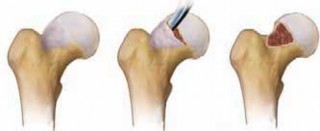

6. The nonspherical portion of the femoral head is assessed using transparent spherical templates (

TECH FIG 6A

).

1. Usually, the nonspherical part of the head–neck junction is located anterolaterally. The transition from

the aspherical to the nonaspherical part usually is characterized by a reddish appearance of the carti-laginous surface.

34. Excess bone is removed, and a smooth femoral neck waist is created (

TECH FIG 6B,C

) using small curved osteotomes.

1. Excessive bone removal during the offset procedure should be avoided, although a resection of less than 30% of the neck diameter does not weaken the femoral neck.